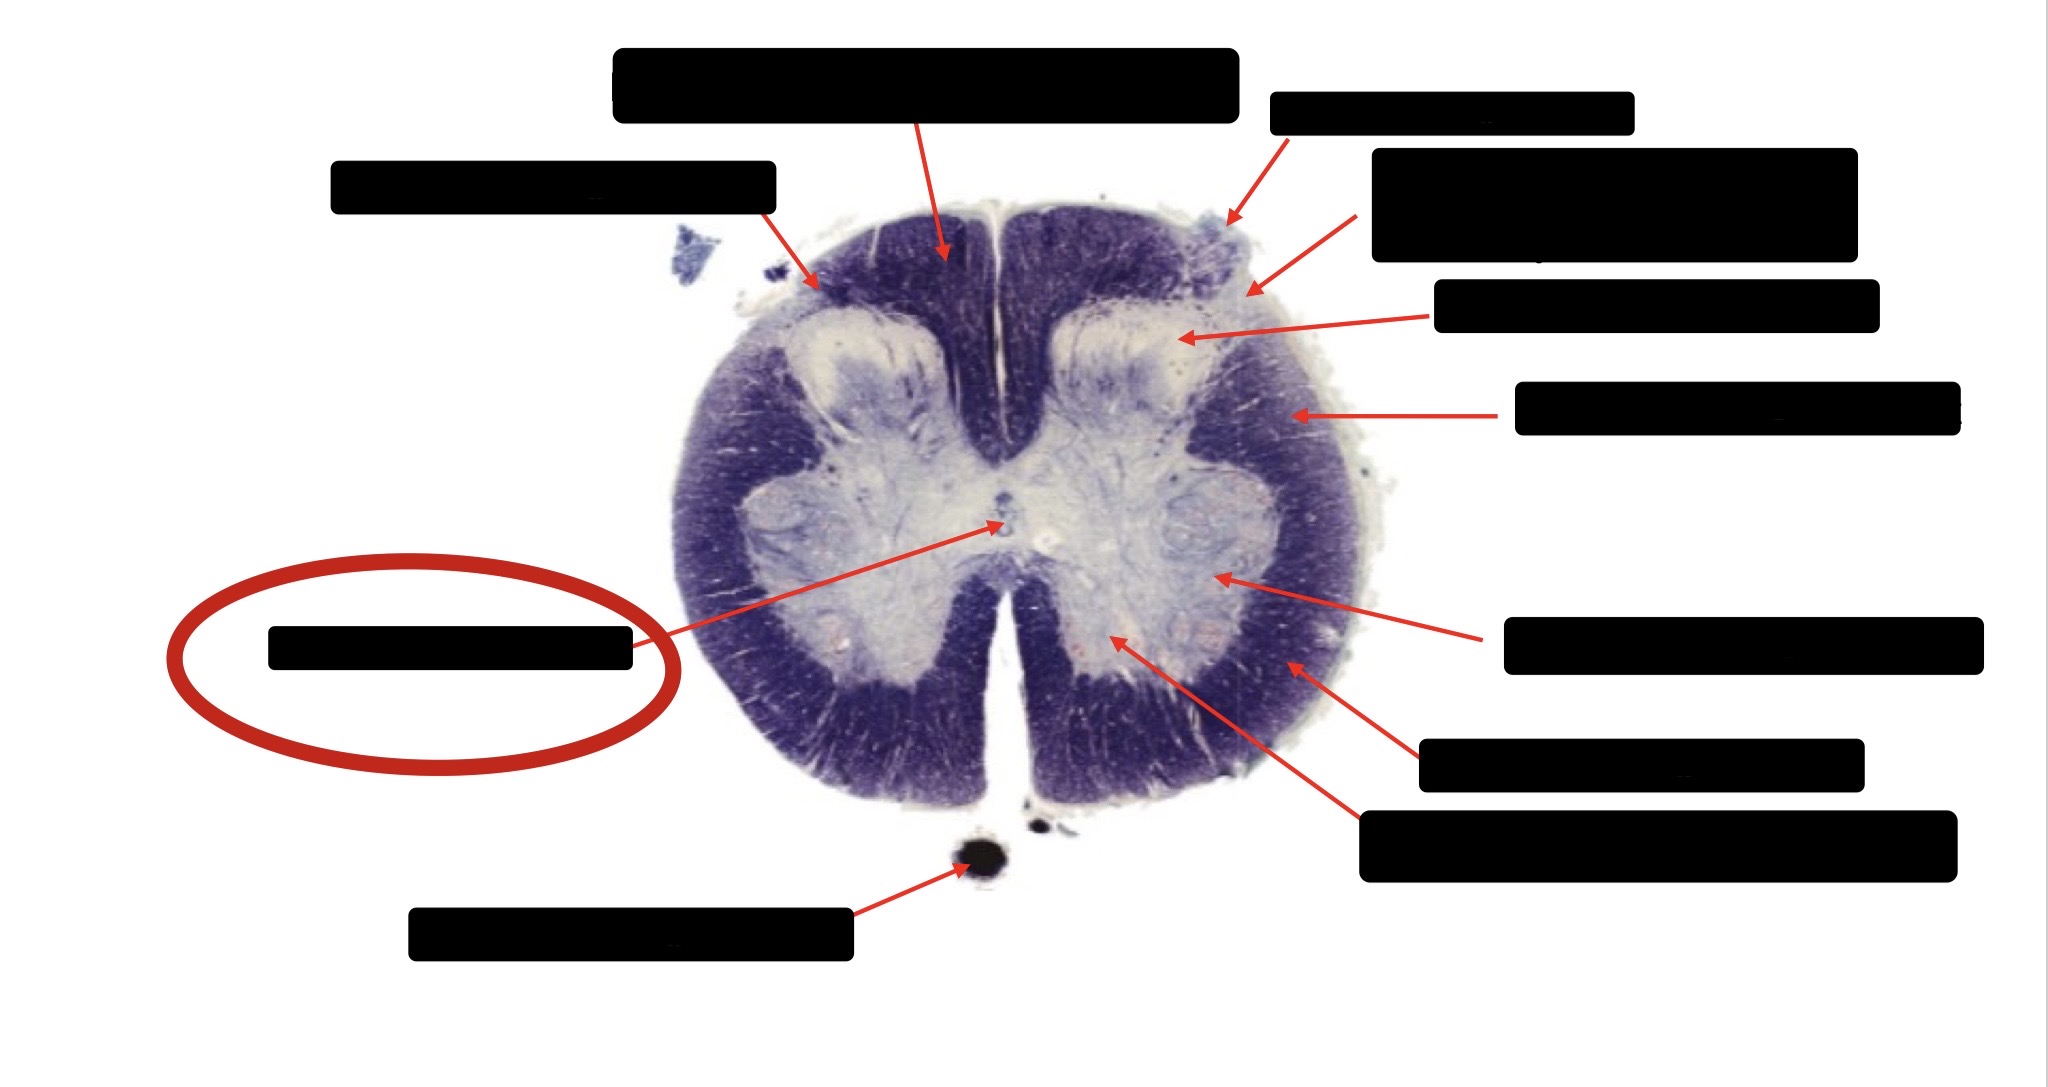

Spinothalmic Tract

Central Canal

Posterior Column (Fasciculus Gracilis)

Large Fiber Entry Zone

Lissaeur’s Tract & Small Fiber Entry Zone

Substantia Gelatinosa

Lateral Corticospinal Tract

Ventral Root Fibers

Anterior Horn Motor Neurons

Anterior Medial Fissure

Dorsal Rootlet

Posterior Spinocerebellar Tract

Anterior Spinocerebellar Tract